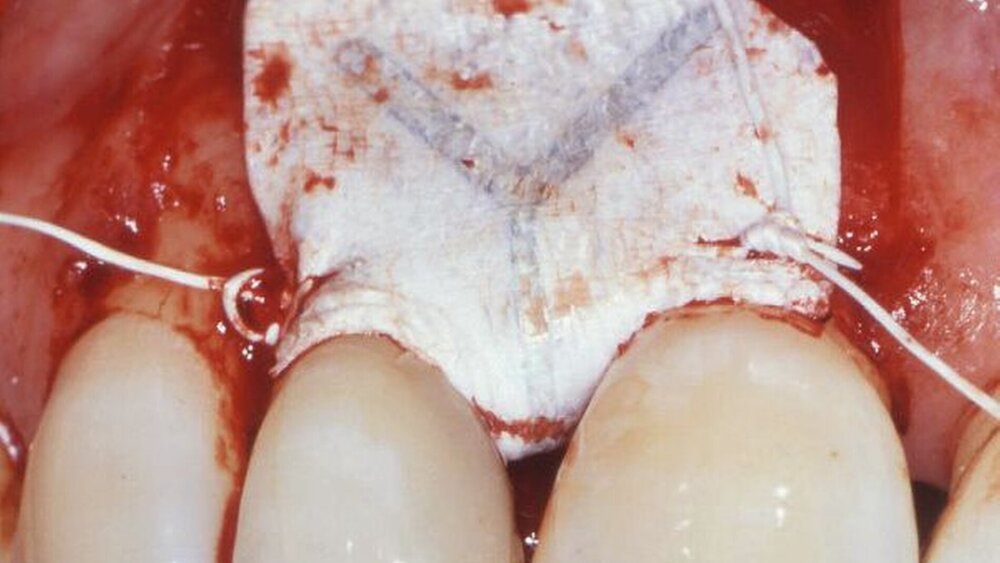

Anschließend ging Cortellini auf die unterschiedlichen Verfahren der Rezessionsdeckung ein. Es existieren verschiedene Techniken der Lappenpräparation. Allgemein ist die Gestaltung des Lappens in Dicke, Spannung und Positionierung wichtig. Auf der Basis wissenschaftlicher Untersuchungen zu jedem der drei Parameter können eine Lappendicke von mehr als 0,8 mm, eine Spannung auf den repositionierten Lappen von 0 bis 4 g und eine Positionierung koronal der Schmelz-Zement-Grenze als günstige Voraussetzungen für eine vollständige Wurzeldeckung postuliert werden.

Cortellini diskutierte im weiteren Verlauf die Rezessionsdeckung mittels Bindegewebstransplantat (BGT) und die möglichen Techniken der Lappenpräparation. In Fall-Kontroll-Studien werden Lappentechniken mit der zusätzlichen Anwendung eines BGT verglichen. In einer Nachuntersuchung von ein bis fünf Jahren konnten bessere Ergebnisse unter Anwendung eines BGT erzielt werden. Während der koronal verschobene Lappen nach einem Jahr zu retrahieren beginnt, nimmt die Rezessionstiefe nach Deckung mittels BGT nach einem Jahr stetig ab.

Tonetti demonstrierte Therapiemöglichkeiten bei vertikalen Knochendefekten mit über 75 Prozent Knochenverlust. In Fall-Kontroll-Studien wurden verschiedene Verfahren verglichen. Wichtig ist, eine möglichst stabile Wundheilung zu erreichen. Einfluss auf diese haben patientenbezogene Faktoren, wie Plaquekontrolle, Nikotinkonsum und genetische Prädisposition, aber auch die Defektmorphologie und die chirurgische Operationstechnik.